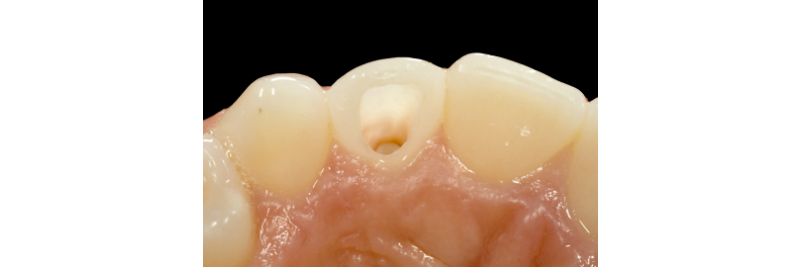

It must be stated that ample access preparation (Figs. 2A, 2B) is not required to internally bleach non-vital teeth, as a larger access preparation further compromises the tooth structurally. Figures 3A and 3B illustrate successful outcomes with a much more conservative approach (treatment by Dr. Steve Baerg, Gig Harbor, Washington).